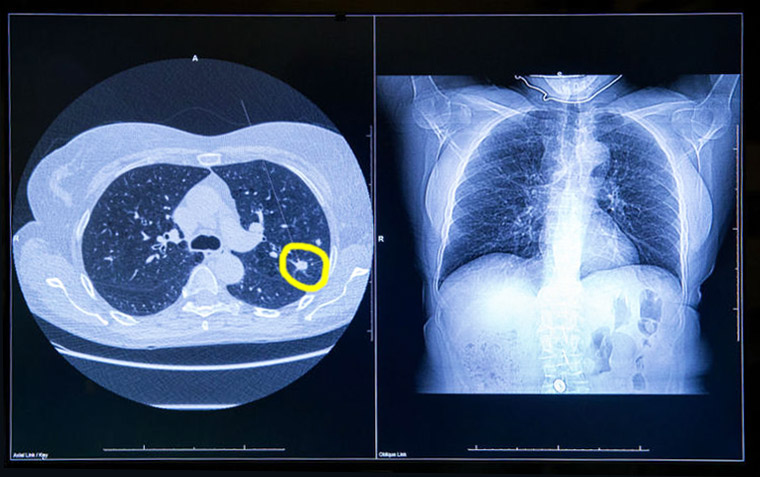

Sobrediagnóstico en el rastreo de cáncer de pulmón

14 agosto 2018